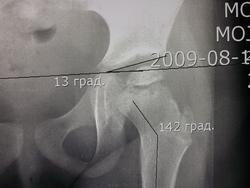

Первоначально обратились с жалобами на боли в левой ноге возникающей утром, в течении 3-х месяцев. В клинической картине походка не нарушена, отмечается укорочение левой ноги 0,5см., приводящяя контрактура бедра, гипотрофиии нет. Вальгусная деформация коленных суставов и стоп. Смущает возраст и пол ребенка. Выставил диагноз Болезнь Пертеса.

Согласна, слева Пертес. А каков возраст девочки?

Возраст девочки 3года 6 месяцев. УЗИ тазобедренных суставов( 02.03.13)- признаки болезни Пертеса.

Похоже, болезнь Пертеса.